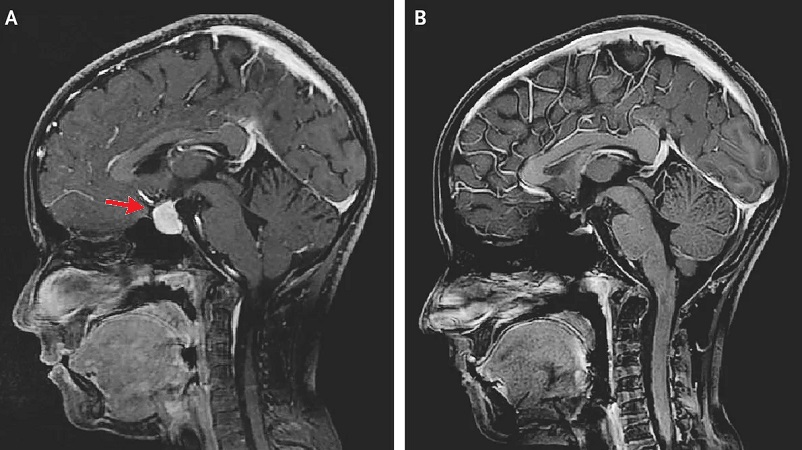

- КТ или МРТ головного мозга позволяет оценить локализацию и размеры опухоли;